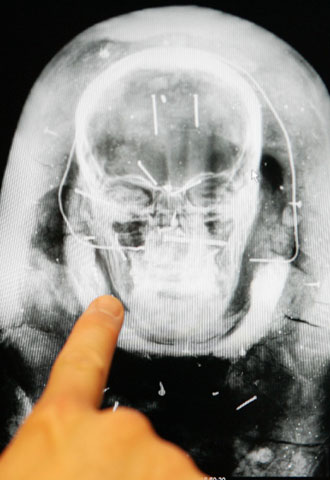

Científicos belgas escanean una momia para reconstruir sus rasgos

Investigadores del Centro Hospitalario Universitario de Lieja (Bélgica) están escaneando minuciosamente la cabeza de una momia egipcia que data de hace 2.500 años, y confían en que los resultados permitirán la reconstrucción de los rasgos que esa persona tuvo en vida, y posteriormente indagar acerca de la identidad del cadáver.

La técnica por escáner permite seguir milímetro a milímetro las líneas de los huesos, incluyendo la dentadura, y lograr separadamente una estructura de la piel. De ese modo, resulta posible reproducir en tres dimensiones el cuerpo analizado.